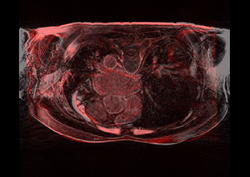

Left) Pre ablation. Right) Post ablation.

Post registered to pre using Slicer pipeline affine registration.